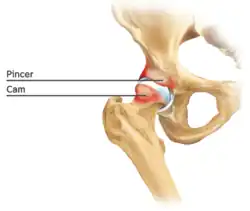

Cam-type femoroacetabular impingement

Cam impingement is created by the abnormal development of the femoral head-neck junction causing what has previously been described as a 'pistol-grip deformity'. This type of deformity is characterised by varying amounts of abnormal bone on the anterior and superior femoral neck at the head-neck junction (see fig. 6). The head-neck junction is at the base of the ball of the hip, where it joins the short neck, which in turn carries on downwards into the femur, or thighbone, itself. A bony protrusion or bump at the head-neck junction has been likened to a cam, an eccentric part of a rotating device. This leads to joint damage as a result of the non-spherical femoral head being forced into the acetabulum mainly with flexion and/or internal rotation. This may impart compression and shear forces to the articular cartilage, and may lead to labral tears and peeling away of the articular cartilage from the underlying bone, so-called cartilage delamination (see fig. 8).[9][10]

Standard arthroscopic treatment of symptomatic cam FAI involves debridement (resection) or repair of any labral [10] and chondral injuries [11] in the central compartment of the hip, and subsequent reshaping of the head-neck junction of the upper femur (osteochondroplasty) in the peripheral compartment [12][13] using high-speed motorised burrs that are similar in design to a dentist's drill (see fig. 9).